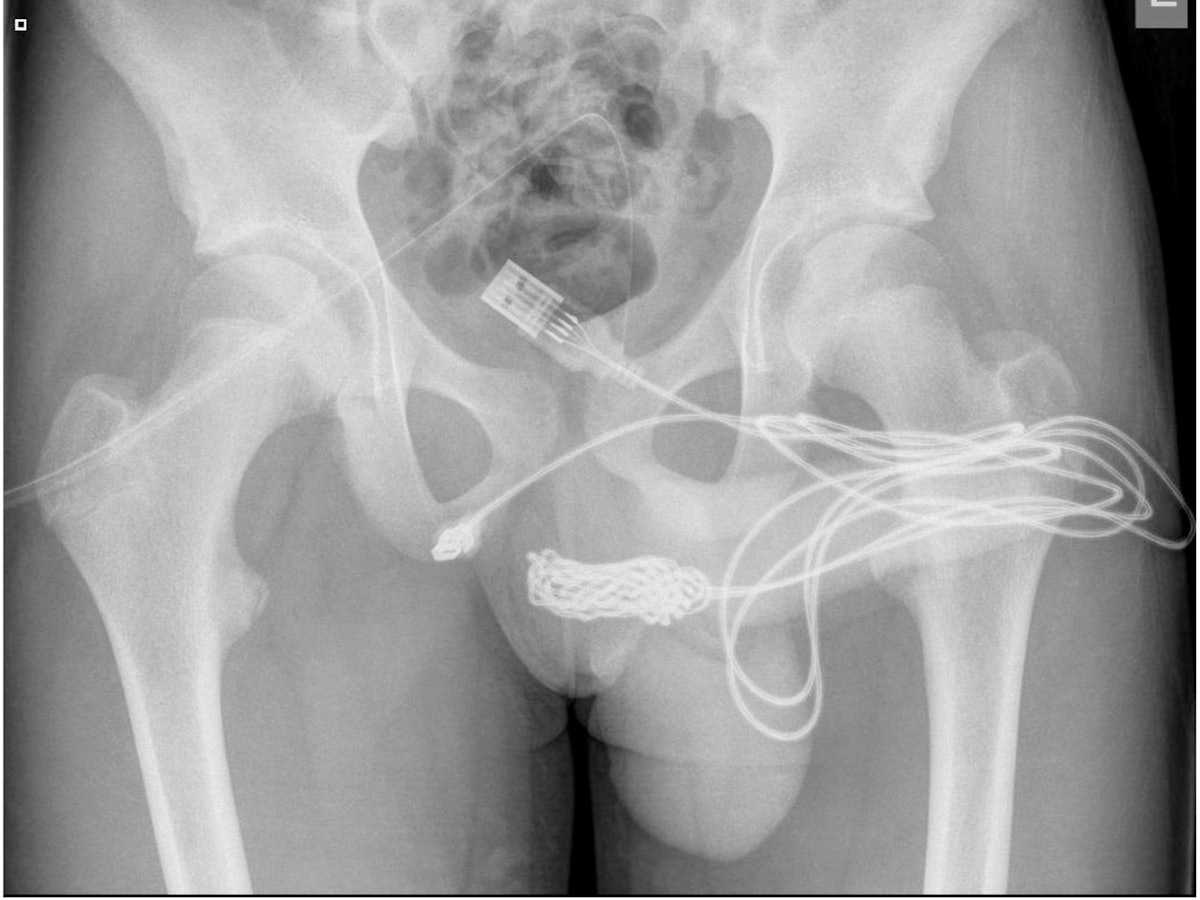

Klaipeda. Zunächst sah es nach einem Routinefall für Ärzte in Litauen aus. Ein Mann wurde mit heftigen Schmerzen ins Krankenhaus eingeliefert. Ein Röntgenbild zeigte dann Unglaubliches.

Wie das Krankenhaus in Klaipeda am Freitag (1. Oktober) berichtete, hatte der Patient mehr als ein Kilogramm Nägel und Schrauben im Magen. Zahlreiche Metallstücke von bis zu zehn Zentimeter Länge befanden sich in seinem Bauch.

In einer dreistündigen Operation holten die Ärzte schließlich sämtliche Schrauben und Nägel aus dem Magen des Patienten. „So etwas habe ich noch nie erlebt“, sagte Chefchirurg Algirdas Slepavicius örtlichen Medien. Der Patient sei nach der OP wohlauf. (afp)